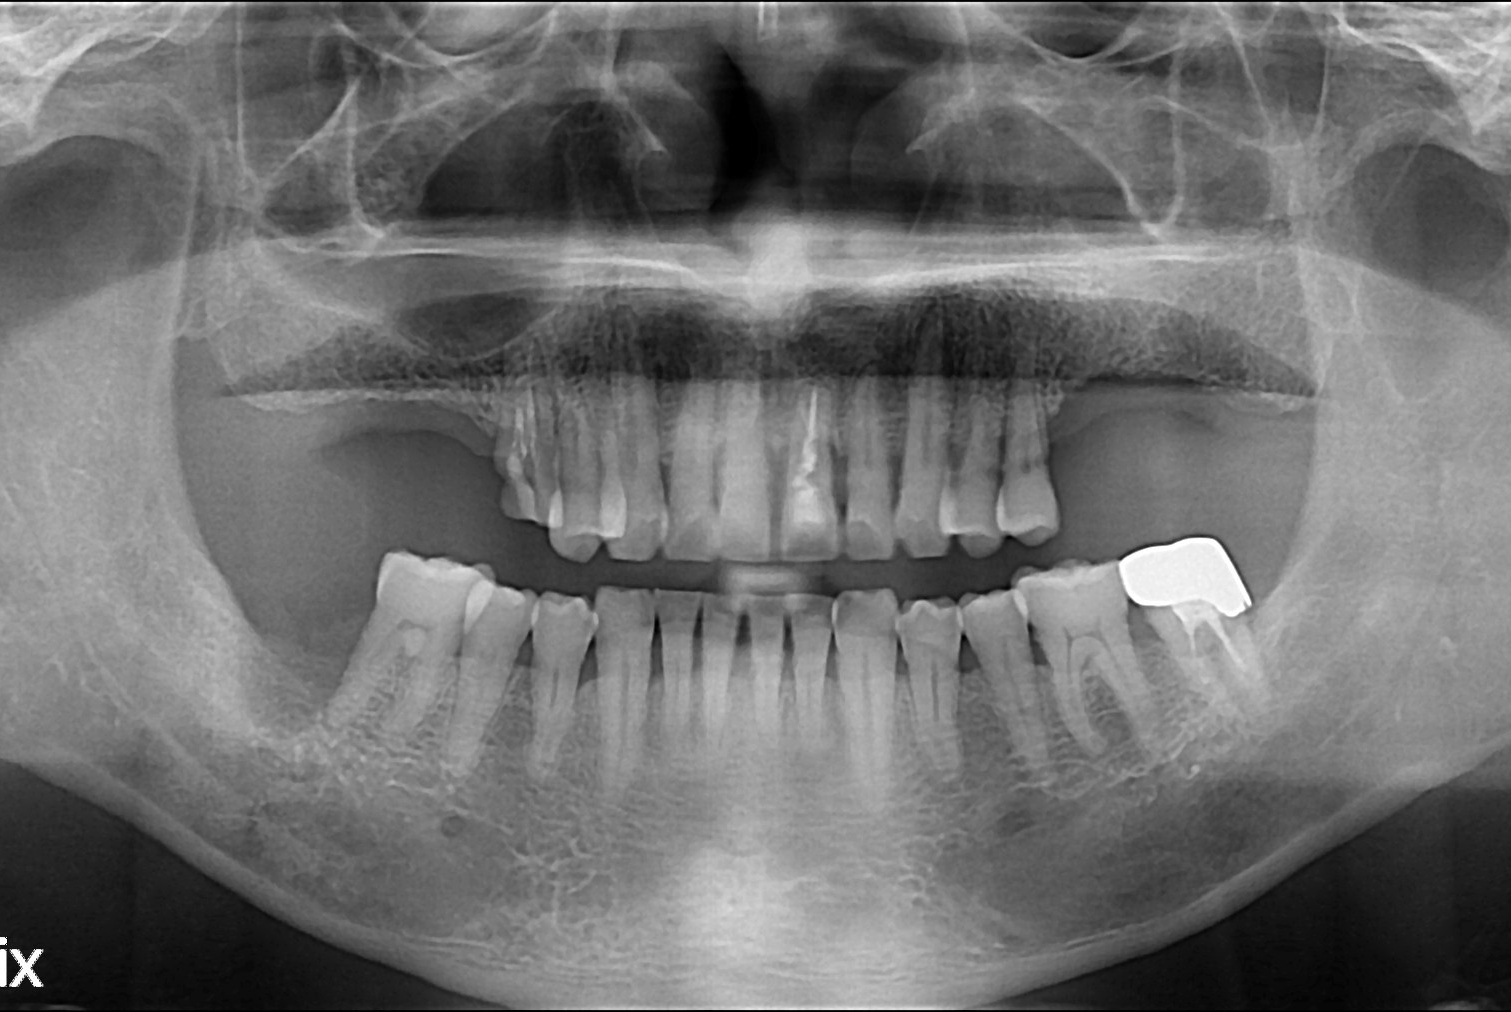

치료전 : 2019-06-13

세종치과는 많은 환자와 다양한 케이스를 바탕으로 항상 편안한 임플란트 수술을 제공하고자 노력하고,

오래동안 튼튼히 쓸 수 있는 임플란트 수술을 가장 큰 목표로 삼고 있습니다